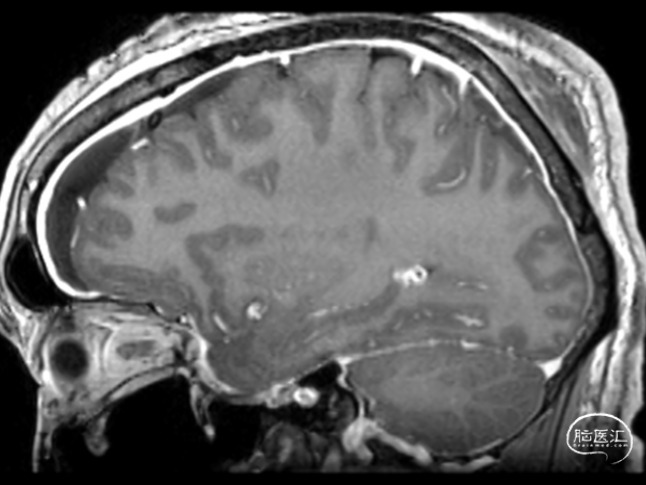

图1:冠状位MRI提示硬脑膜弥漫性增强。